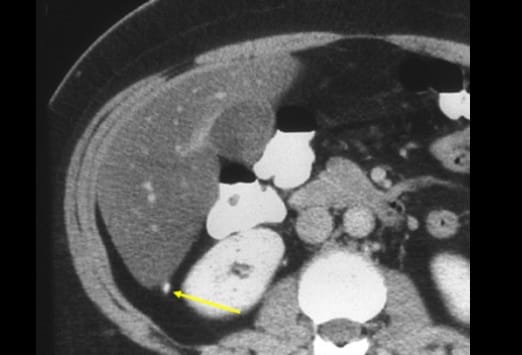

In dieser Abbildung reicht die Appendix hinauf bis zur Leber. Die Appendix liegt in bis zu 65% der Fälle retrocoecal. Bei Patienten mit einer retrocoecal gelegenen Appendizitis ist der Schmerz oft schlecht zu lokalisieren. Diese Patienten geben diffuse Beschwerden beim Husten oder Schmerzen in der in der Flanke an, seltener haben sie Schmerzen im rechten Unterbauch. Bei bis zu 15% der Patienten kann die Appendix nicht dargestellt werden. Dies gilt insbesondere bei Patienten mit einem geringen Anteil von intraabdominellem Fett. Von einigen Ärzten wird behauptet, dass eine nicht darstellbare Appendix eine Appendizitis ausschließt, [3] allerdings kann eine nicht erfolge Lokalisationsdiagnostik in diesen Fällen zu einer falsch-negativen Diagnose führen. In diesen Fällen ist es sinnvoll, eine engmaschige Verlaufskontrolle zu empfehlen.